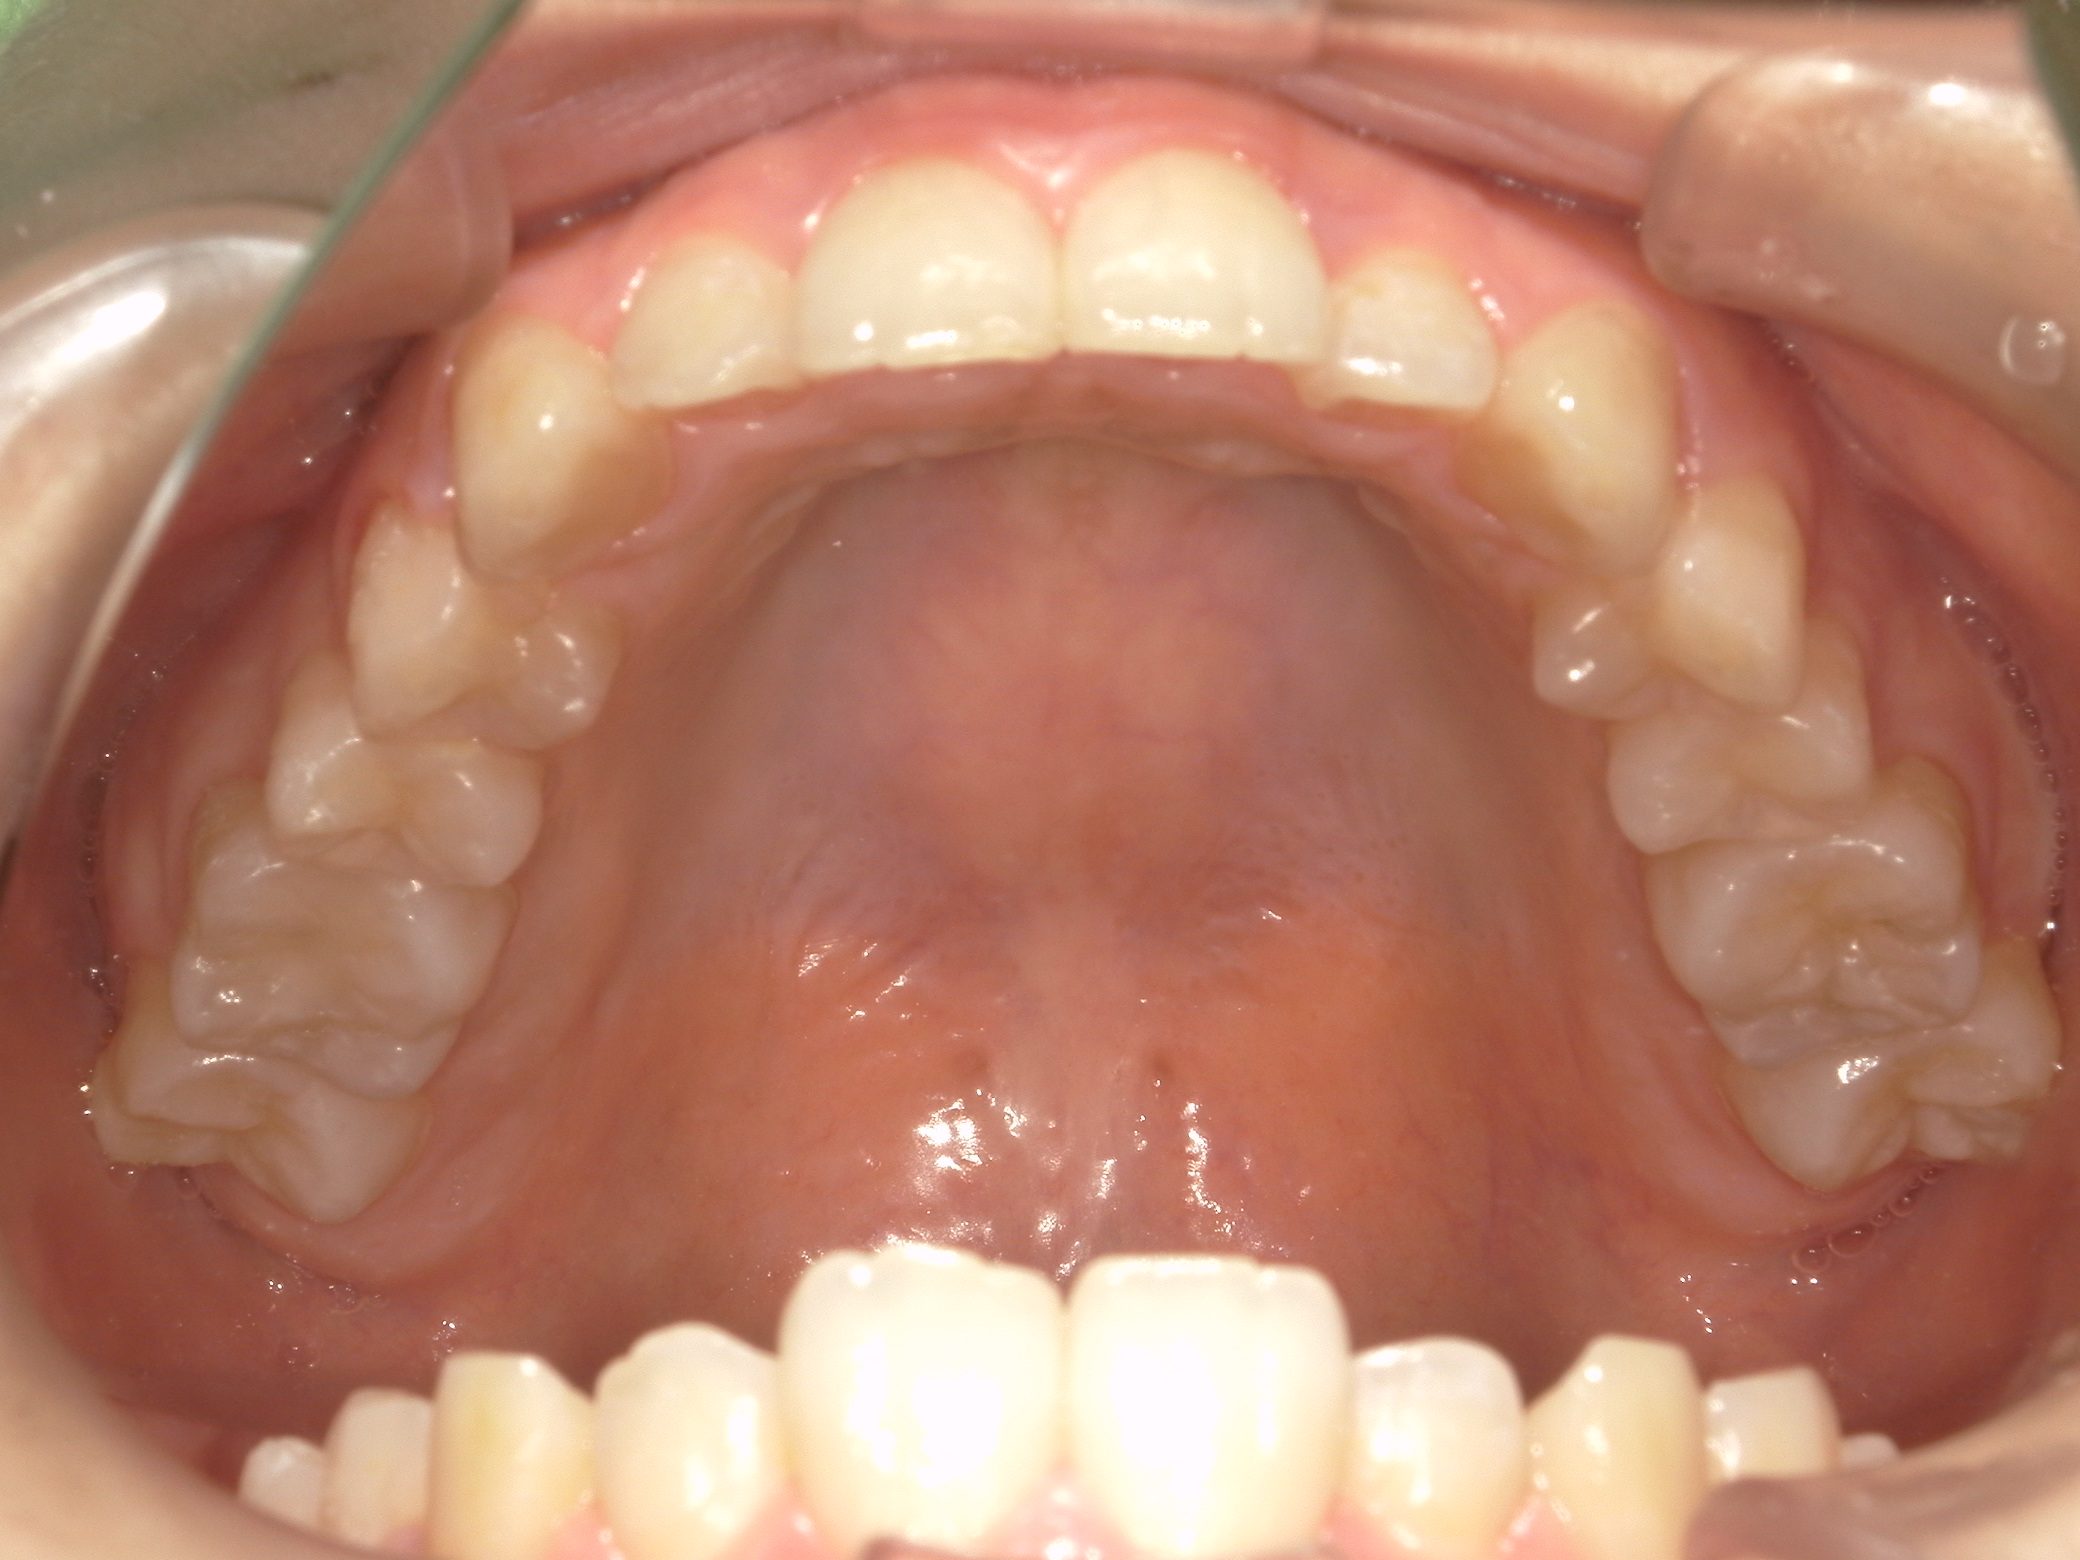

Before

After